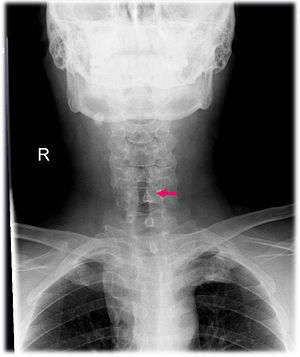

| Neck AP x-ray of patient with post-intubation subglottic stenosis, as shown by the narrowing in the tracheal lumen marked by the arrow. | |

Subglottic stenosis is a congenital or acquired narrowing of the subglottic airway. Although it is relatively rare, it is the third most common congenital airway problem (after laryngomalacia and vocal cord paralysis). Subglottic stenosis can present as a life-threatening airway emergency. It is imperative that the otolaryngologist be an expert at dealing with the diagnosis and management of this disorder. Subglottic stenosis can affect both children and adults.

Subglottic stenosis can be of three forms, namely congenital subglottic stenosis, idiopathic subglottic stenosis (ISS) and acquired subglottic stenosis. As the name suggests, congenital subglottic stenosis is a birth defect. Idiopathic subglottic stenosis is a narrowing of the airway due to an unknown cause. Acquired subglottic stenosis generally follows as an after-effect of airway intubation, and in extremely rare cases as a result of gastroesophageal reflux disease (GERD).